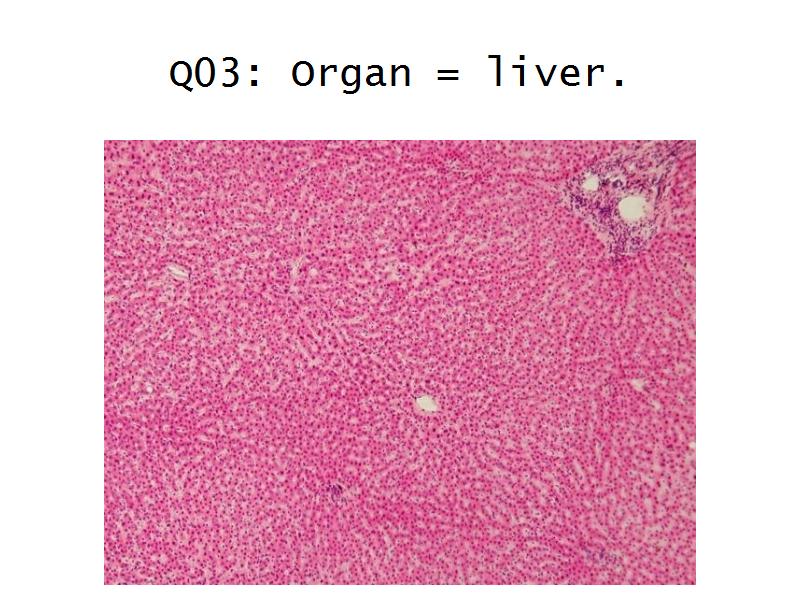

- Liver =

- Liver = squamous, cuboidal